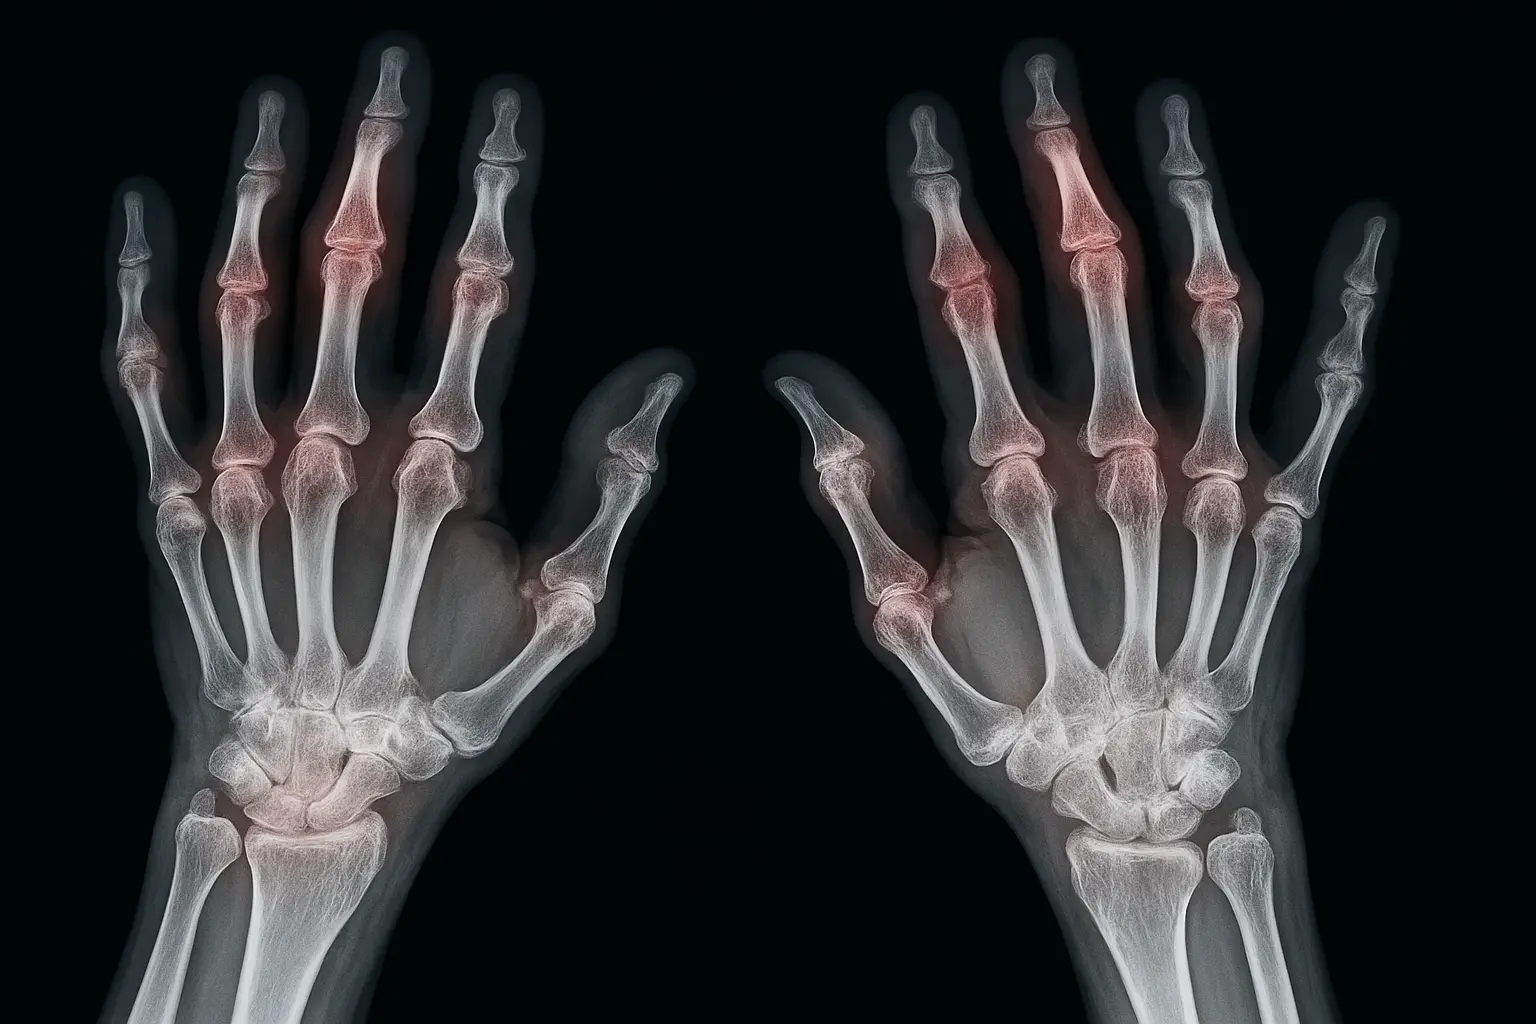

При ревматоидном артрите преимущественно поражаются суставы, которые расположены симметрично. Болезнь начинается с мелких суставов кистей и стоп, постепенно воспаление распространяется на более крупные сочленения. Места поражения зависят от стадии болезни, индивидуальных особенностей организма.

- Суставы кистей. Чаще всего воспаляются пястно-фаланговые и проксимальные межфаланговые суставы. Появляется боль при сжатии кулака, скованность по утрам, затем появляются деформации пальцев.

- Симметричность поражения. Преимущественно поражаются суставы обеих кистей, стоп, запястий, коленей. Это помогает отличить болезнь от других форм артритов.

Инструментальная диагностика

Рентгеновский снимок выявляет эрозии, сужение суставной щели, признаки остеопороза. УЗИ и МРТ обнаруживают воспаление в суставах раньше, чем это становится заметно на рентгене. Согласно международным критериям РА, диагноз устанавливается при наличии характерной клиники, лабораторных маркеров, типичных рентгенологических признаков.